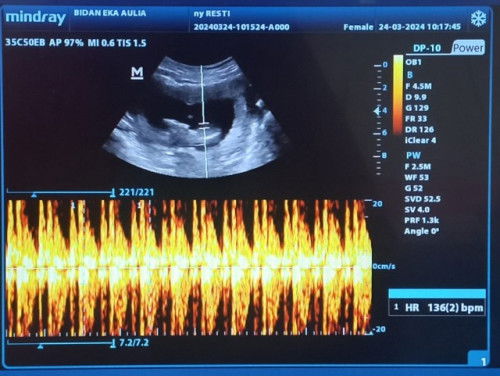

Hasil USG usia kandungan 13w2d

MasyaAllah Alhamdulillah uk 13w3d sudah terdengar djj, Anak ke 2 .. Sehat sehat untuk diriku, calon anakku, dan untuk semua bumil ...